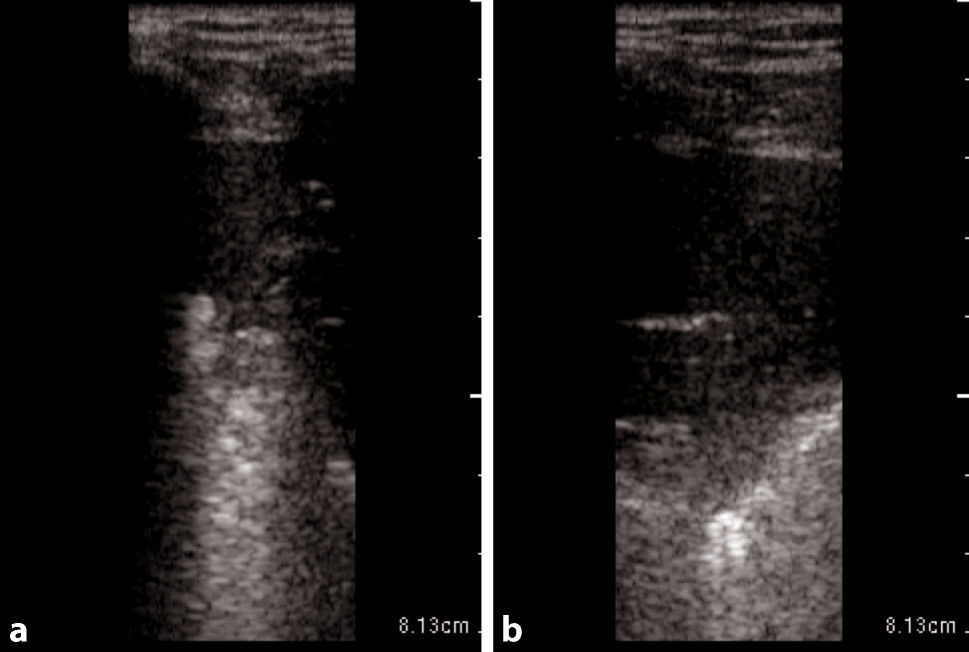

Fig. 1

Large anterior consolidation of the lung in POCUS in a longitudinal plane on the right anterior hemithorax in critical COVID-19. a and b stays the same as the intro provides the information needed in both images

Typical LUS findings in patients with COVID-19 pneumonia are bilateral areas of fragmentation and irregularities of the pleural line, sometimes with massive reverberation artifacts (recently named light beam appearance), small subpleural consolidations, and a reduction or absence of pleural sliding [24]. Reverberation artifacts arising from a fragmented pleural line are indicative of diffuse alveolar damage, diffuse parenchymatous lung diseases, or inflammatory diseases such as COVID-19 [28]. As the disease progresses, consolidations can be seen (Fig. 1). Small consolidations and subpleural consolidations are typical, yet not specific to COVID-19 [26]. As seen on ultrasound images, consolidations can be described as hypoechoic areas with small hyperechoic structures within (bronchograms), in combination with a tissue-like appearance or hepatization of the lungs [31, 32]. If there is a consolidation of an entire lobe, the borders will be well defined, whereas in smaller consolidations, the deeper borders appear irregular, described as the shred sign [33]. As lung ultrasound may help to predict the clinical course and outcomes of patients with COVID-19, and for follow-up purposes, the authors recommend a quantification of reverberation artifacts (Fig. 2), and suspected areas of consolidation (Figs. 1 and 3; Table 1; [24, 34]).

Table 1

Suggested measurements—size quantification of consolidation

Consolidation

Small

0.5 ≤ 2 cm

Moderate

2 ≤ 5 cm

Large

> 5 cm